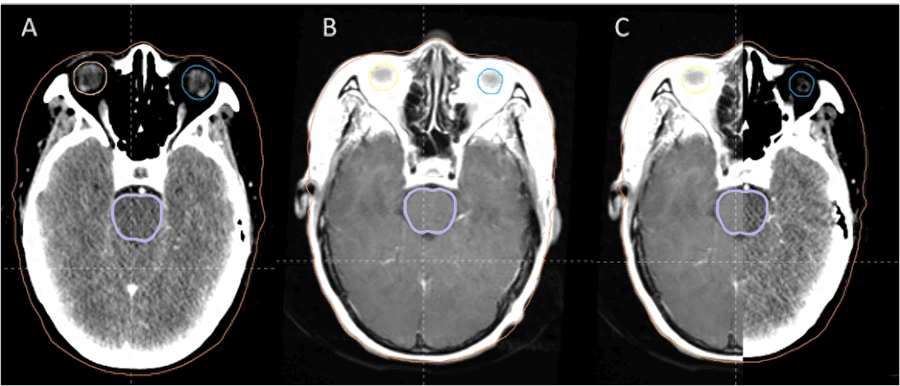

近日南华大学附属第二医院肿瘤中心成功开展了基于深度学习的智能放疗靶区勾画与图像精准融合/配准。

肿瘤中心二区主任成浩博士介绍:在放疗靶区勾画阶段是基于增强CT图像,但CT图像在软组织坏死,水肿等区域成像质量不如核磁共振(MRI)。因此在头颈部和盆腔等特定位置的肿瘤靶区勾画必须结合磁共振定位扫描。

脑部肿瘤配准效果图